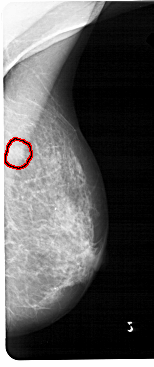

FILE: A_1473_1.RIGHT_CC.OVERLAY

TOTAL_ABNORMALITIES 1

ABNORMALITY 1

LESION_TYPE MASS SHAPE IRREGULAR MARGINS ILL_DEFINED

ASSESSMENT 4

SUBTLETY 3

PATHOLOGY BENIGN

TOTAL_OUTLINES 1

BOUNDARY